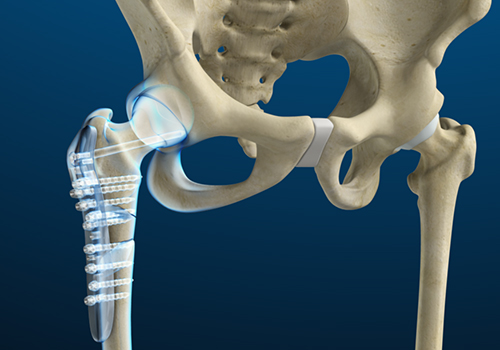

Revision hip replacement is a complex surgical procedure in which all or part of a previously implanted hip joint is replaced with a new artificial hip joint. Total hip replacement surgery is an option to relieve severe arthritis pain that limits your daily activities.